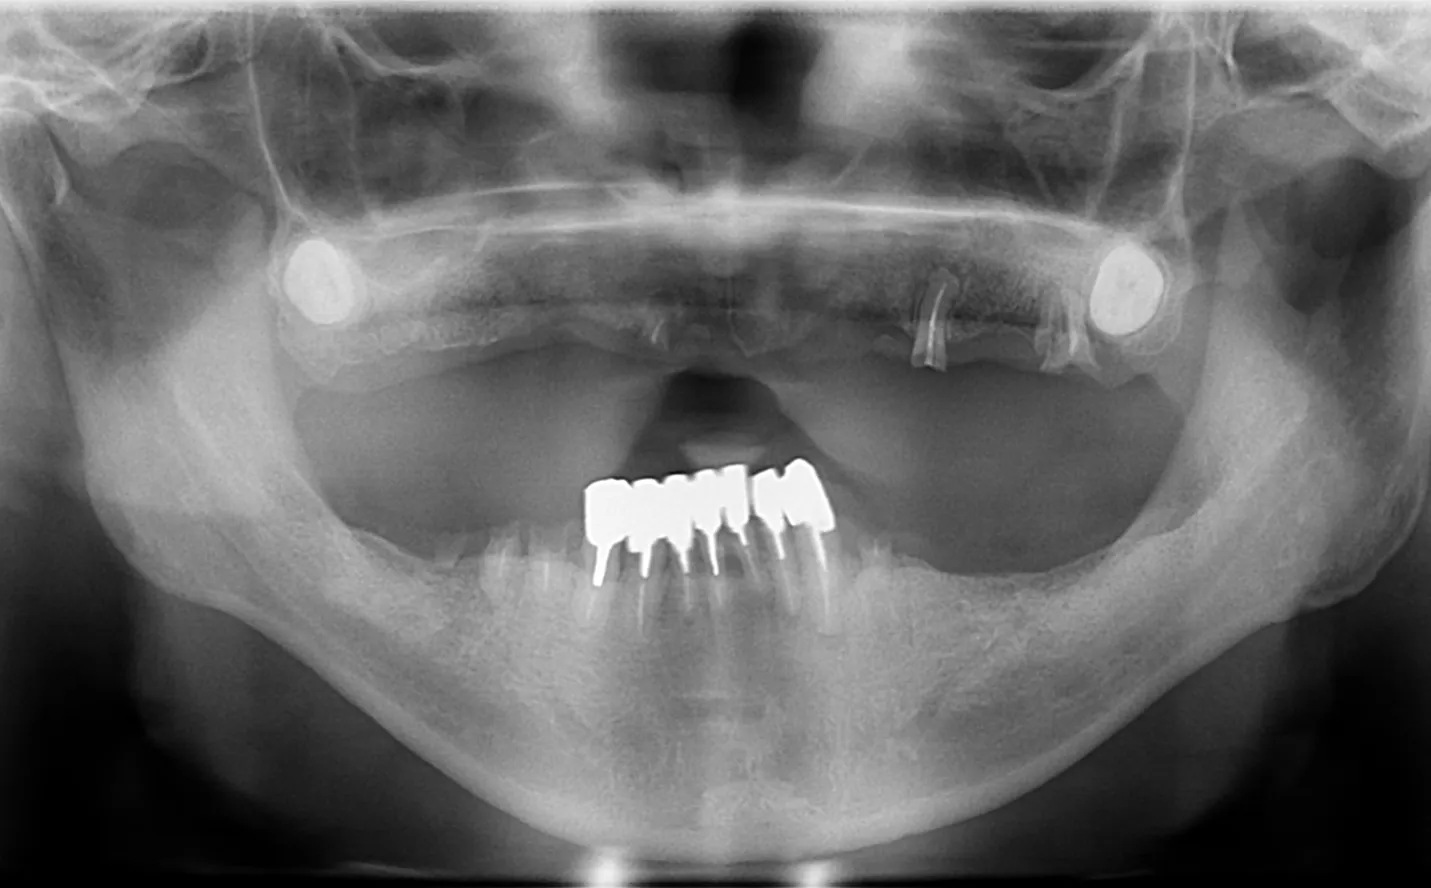

【症例1】

主訴

噛めない。不自由なく食事をしたい。

年齢・性別

50代男性

治療内容

上下顎フルインプラント

期間

1年2ヶ月

費用

7,279,000円